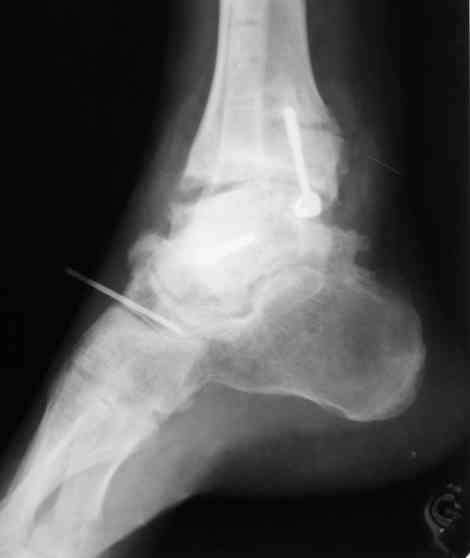

И второй случай из недавней ташкентской практики, (извините за качество ренгенограммы и только в одной проекции) случай падения с высоты (кстати моего друга - известного киноактера) - открытый

смещенный перелом тарана, с переломом переднего края дистального эпиметафиза большеберцовой кости.

При поступлении в приемной сделана первичная обработка с ушиванием открытой латеральной раны и вытяжением за пятку.

Из-за отсутствия времени пришлось оперировать на второе утро, из материала, что имеем на месте, фиксирован двумя шурупами, а третий-это контур сломанного жойстика в 4 мм. На дистальный медиальный конец тибиа antiglide 3.5 мм пластина. Через пару дней выписан и несмотря на предупреждение, самостоятельно начал нагрузку в 4 недели, время не ждет, снимается в боевике в Росийской Федерации.